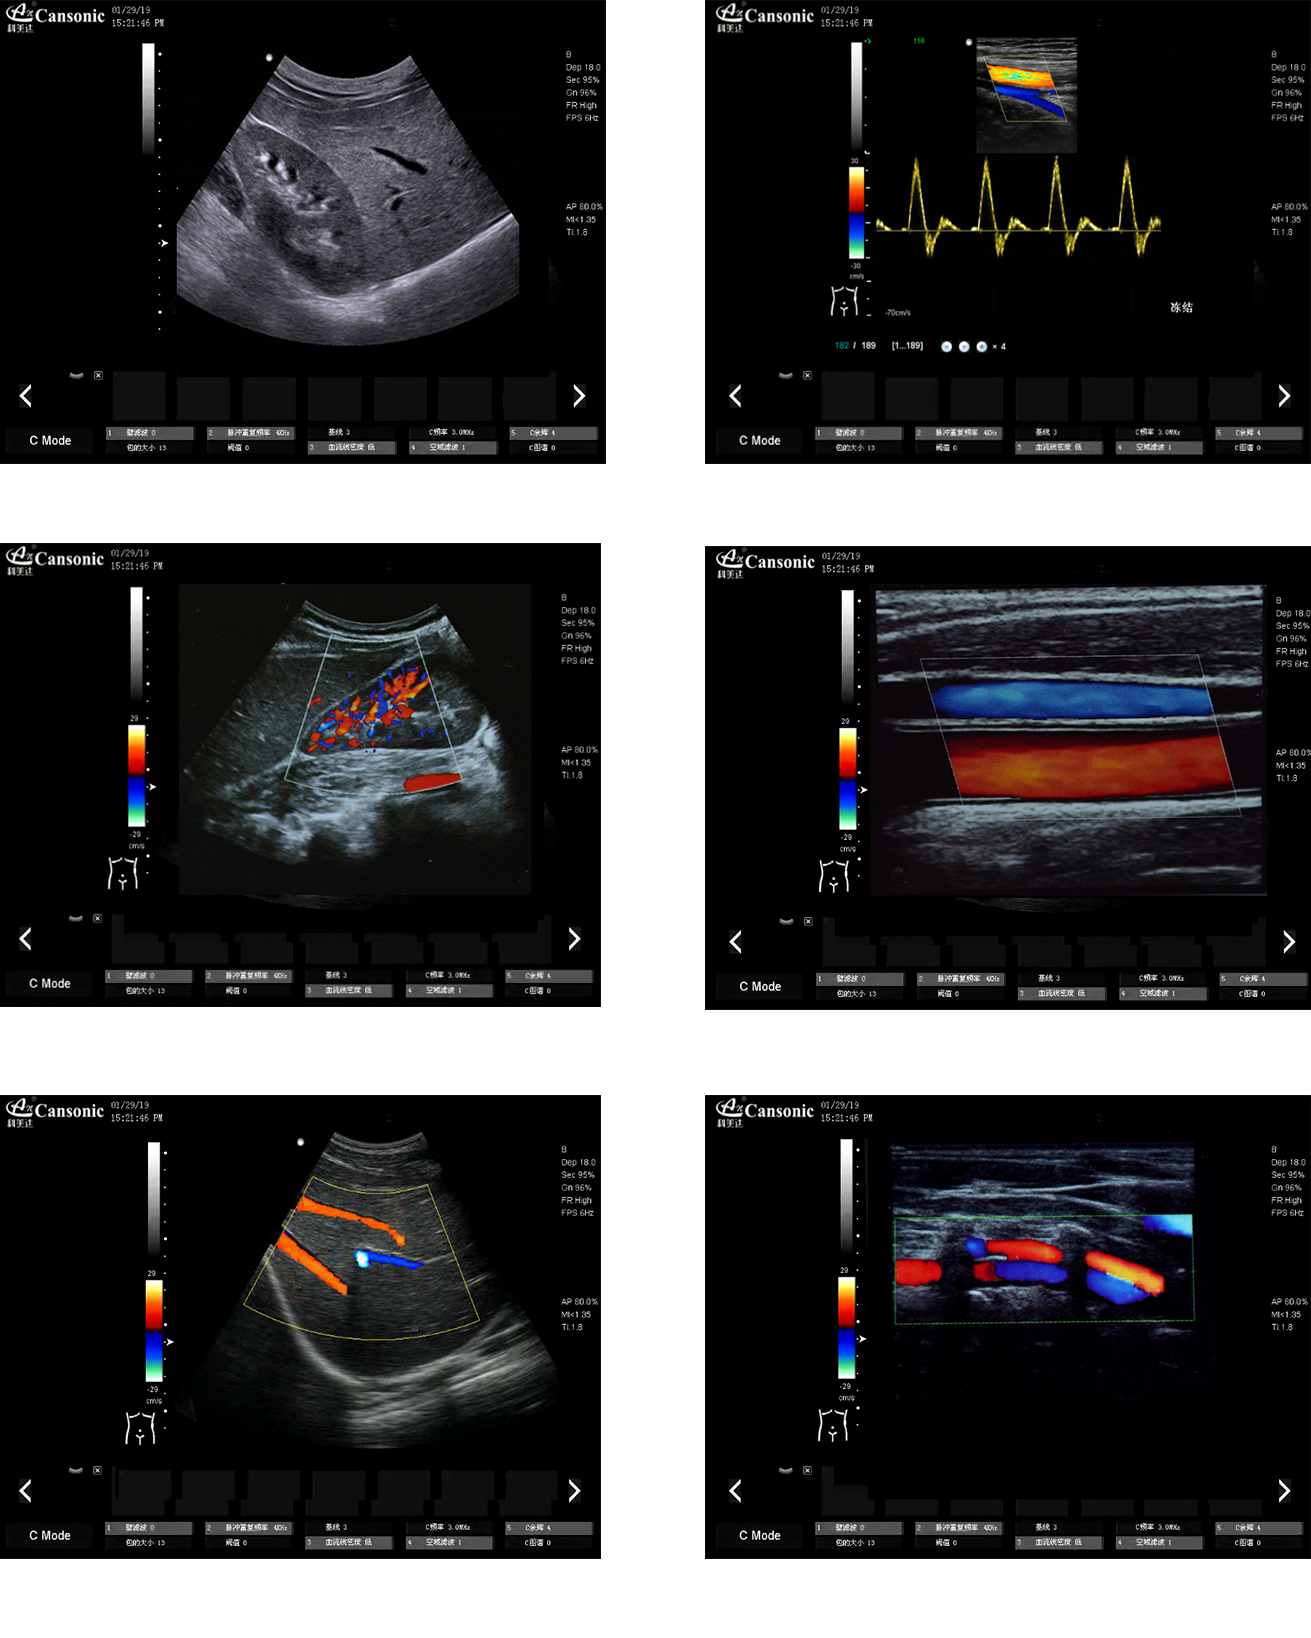

科美達K10圖像實例

1、薈萃前沿成像技術(shù),以優(yōu)異的圖像質(zhì)量滿足全面的臨床應(yīng)用

2、融合高端硬件工藝及智能后處理算法,大幅提升運算速度

3、脈沖反相諧波功能,提高軸向分辨率,減少圖像偽影,提高診斷率

4、選擇手動或自動包絡(luò)頻譜,提高效率,一鍵顯示各種血流動力學(xué)數(shù)據(jù)

5、精準濾波技術(shù),降低噪聲干擾,提升血流靈敏度。